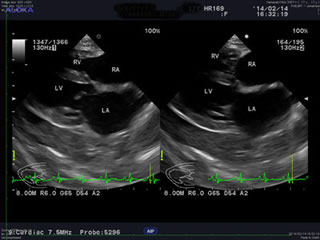

一応 心臓心電図 と 心臓エコー検査 、

そして毎度の 血液検査 と 尿検査 が

8:00前に行えたのでそれはそれで良かったかですが?